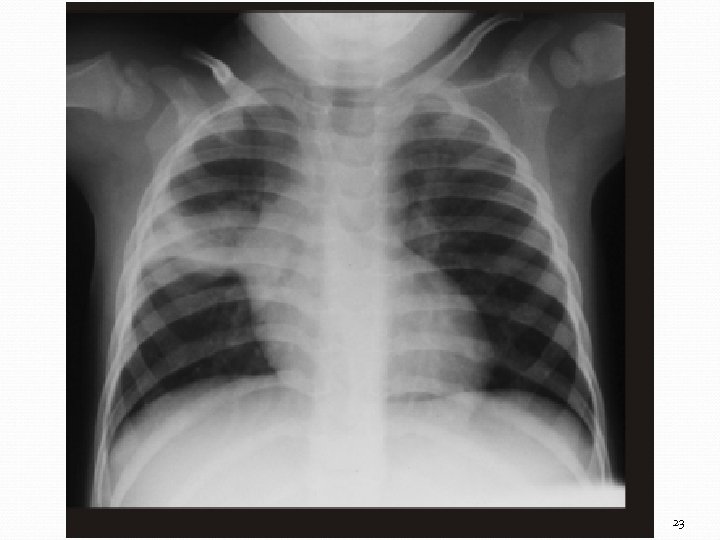

Complexe primaire avec une consolidation- atéletasie ségmentaire au sommet du lobe supérieur droit 23

Diagnostic Test à la tuberculine (positif dans 0 -30%) Radiographie utile dans les cas de suspicion de TB pulmonaire ou miliaire Diagnostic microbiologique Frottis d’aspirations gastriques, crachat induit, LCR ou autres liquides corporels (immunofluorescence plus sensible) Cultures (milieu L-J, système bactec ~ 2 semaines) Diagnostic histologique Techniques moléculaires (PCR, Sérologie) 21